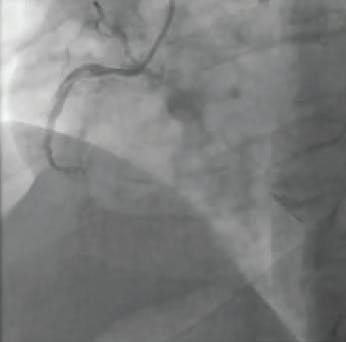

INTERVENTION

Angiography showed complete occlusion and heavy thrombus burden from the SVG to the diagonal branch (Figure 1). It was planned to intervene upon the lesion. The occlusion was determined to be acute based on a previous angiogram within the past month that showed a patent SVG to the diagonal branch. The lesion was wired using a 0.014-inch X 300-cm Sion® Blue wire (Asahi Intecc USA, Inc.) without any problems. Because the graft was totally occluded, it was decided not to advance a filter through the occlusion due to risk of distal embolization (Figure 2). Mechanical thrombectomy with CAT RX was used to aspirate the thrombus. After three runs of mechanical aspiration using a CAT RX and around 3 minutes of aspiration, TIMI 3 flow was restored (Figure 3). The patient was treated with heparin infusion overnight to reduce further thrombus burden and was brought back to the catheterization laboratory the next day for staged PCI with a DES (Figure 4).

Figure 1. Initial angiogram showing occlusion through the SVG.

Figure 2. Angiogram after wiring.

Figure 3. TIMI 3 flow through the SVG after using CAT RX.